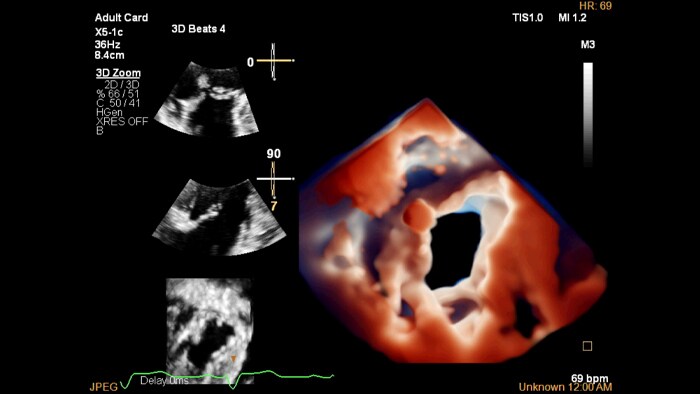

Функциональный дизайн. Датчик X5-1c с многоплоскостной реконструкцией и системой трехмерной фотореалистичной визуализации Cardiac TrueVue

Фотореалистичная визуализация в 3D-эхокардиографии

Виртуальный источник света подсвечивает структуры и увеличивает глубину восприятия для улучшенной интерпретации изображений при заболеваниях сердца.